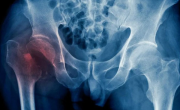

La enfermedad silenciosa que produce fracturas en una de cada tres mujeres de más de 50 años

El Destape Sociedad 20/Oct/2025

Salud La enfermedad silenciosa que produce fracturas en una de cada tres mujeres de más de 50 años Ésta afección perjudica a más de 500 millones de personas a nivel mundial y suele no provocar síntomas hasta que es demasiado tarde.  20 de octubre, 2025 17.56 Este 20 de... + más